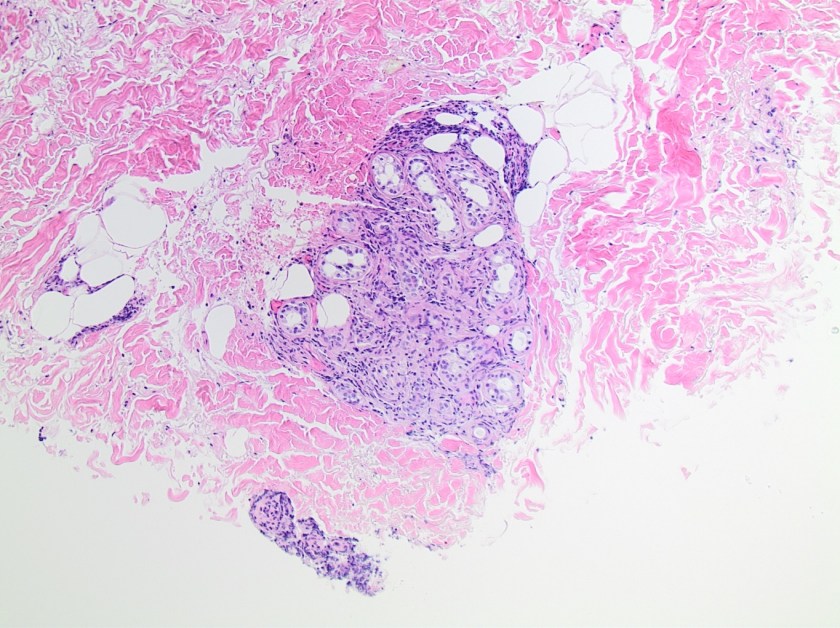

On histologic examination of the skin biopsy, nodular, superficial and deep granulomatous inflammation was noted surrounding eccrine glands and engulfing nerves (Images 1-3). Fite staining illustrated numerous acid fast bacilli (Image 4) and, given the geographic location of the patient and clinical symptoms, was felt to be highly suggestive of Mycobacterium leprae. The case was sent for confirmatory testing by polymerase chain reaction (PCR). All cultures collected were negative.

The diagnosis of M. leprae is largely a clinical one as the organism is not able to be grown on artificial media, but histology and confirmatory PCR are useful adjuncts. Skin biopsies should be full thickness and include the deep dermis. Ideally, the most active edge of the most active lesion should be biopsied. There is a spectrum of M. leprae which ranges from few lesions and a paucity of bacilli (tuberculoid leprosy) to widespread skin involvement with numerous bacilli (lepromatous leprosy). Histologically, there are granulomatous aggregates of epithelioid cells, multinucleate giant cells and lymphocytes and inflammation often engulfs sweat glands and nerves. Small lesions that have poorly defined borders and are found on the elbows, knees or ears are where bacilli tend to be located. A Fite stain is useful to highlight the acid fast bacilli located in the macrophages within the inflammatory nodules. M. leprae PCR can also be performed on blood, urine, nasal cavity specimens and skin biopsies as a sensitive diagnostic technique. PCR can also be used to detect certain genes that confer resistance to common treatment drugs such as rifampin, ofloxacin and dapsone.